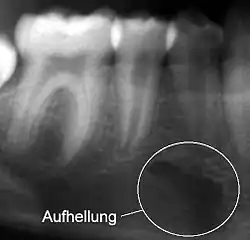

Eine Verschattung (auch Radioopazität) ist ein heller und eine Aufhellung (Radioluzenz) ein dunkler Bereich auf einem Röntgenbild.[1] Grund ist die unterschiedliche Röntgenopazität von Gewebearten.

Da die Begriffe aus der Ära des Fluoreszenzradiographie beibehalten wurden, liegt ein scheinbares Paradoxon vor. Es wird also ein Bereich auf dem Röntgenfilm, der heller ist, als er sein sollte, verschattet genannt und ein Bereich, der dunkler ist, als er sein sollte, aufgehellt genannt.